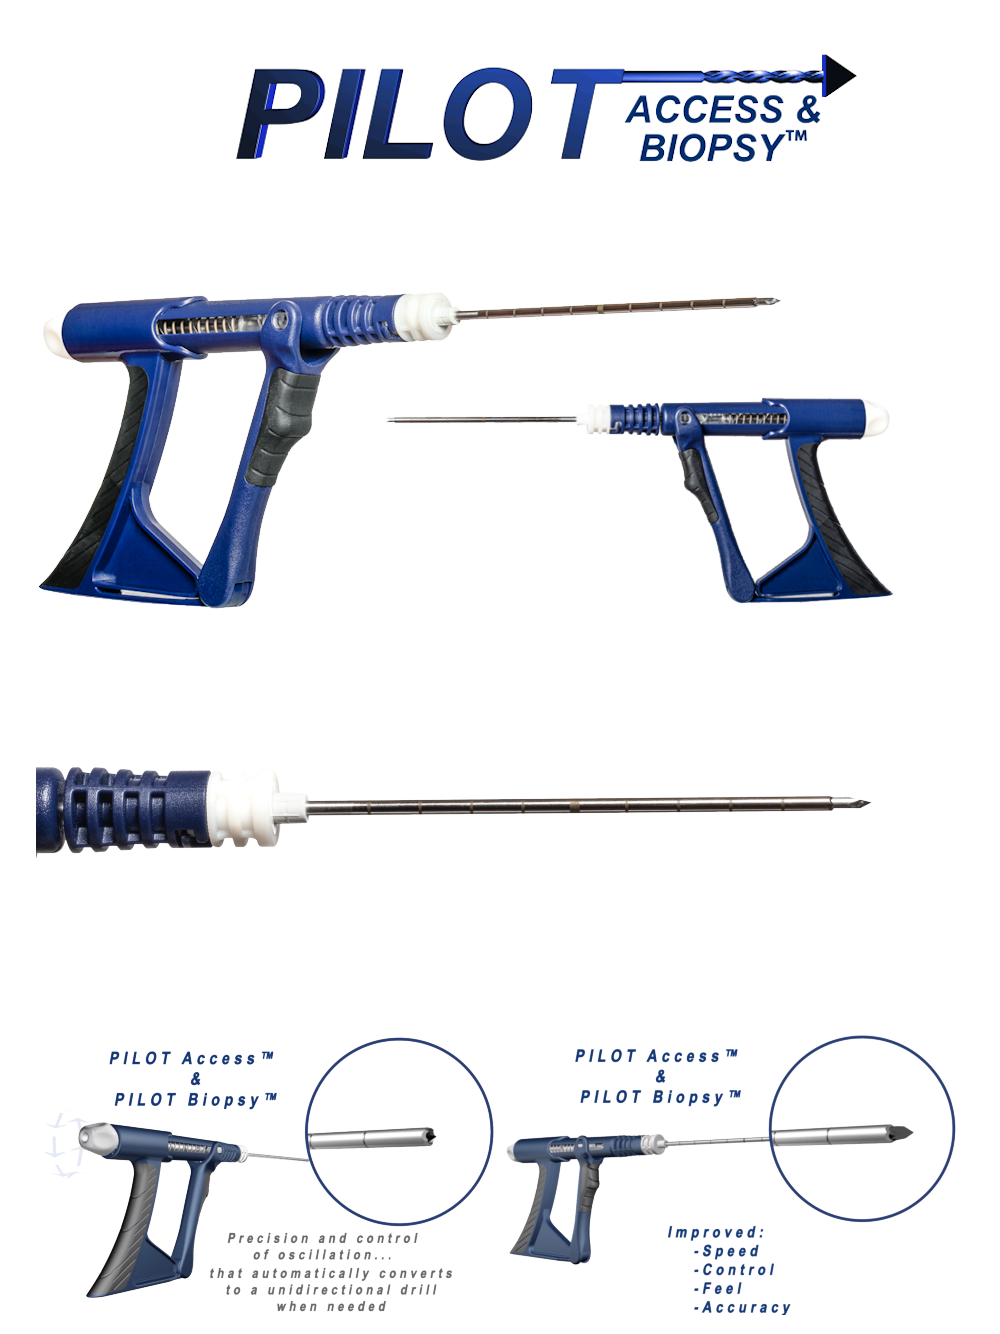

PILOT ACCESS & BIOPSY ™

Bone access and percutaneous biopsy may be performed with a variety of devices, systems, and techniques including basic manual devices and electromechanical drill-like systems.

Basic manual devices are cost-effective and easy-to-use, but often lack speed, power, control, and effectiveness. Electromechanical systems may improve speed and power for certain cases, but may require costly capital equipment, service contracts, complex set-up, and expensive disposables. Some electromechanical systems reduce physician tactile “feel” for the procedure and may introduce new risks that outweigh their benefit.

The PILOT is a single-use, non-powered, hand-held, and hand-manipulated tool designed to combine the benefits of basic manual devices and electromechanically powered systems.

Clinicians squeeze and release the handle with their fingers to actuate. Improved control means physicians can perform percutaneous biopsy and/or bone access based on what they see and feel during the procedure.

INDICATIONS FOR USE: The PILOT Access & Biopsy 11ga 10cm device is a non-powered, hand-held, and hand-manipulated manual surgical instrument designed for bone access and percutaneous biopsy. PILOT devices are “tools” not “treatments.”